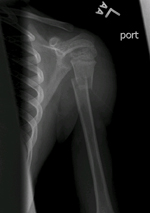

Our brand new hospital recently opened and was the closest, so off we went. Everyone we encountered was so nice, and they also gave him something for the pain pretty quickly. From the moment they cut off his shirt, it was easy to see a break was obvious. The x-ray technician brought me to the x-ray directly and it didn't take any words from her for the tears to come to my eyes - the picture said it all. It was very obvious this situation wasn't good. His humerus was completely cracked in half, and not lined up. Not humorous at all. See for yourself:

An orthopedic surgeon explained he'd give Connor some analgesic to make him groggy and unaware, and he'd try to manually reset the bone back into place. After he came out of that, he didn't remember any of it, but I always will. Watching his eyes dilate and him slip into another zone was very difficult. Worse was watching the doctor try to wretch the bones back in place. Seeing some tears fall from his eyes made mine do the same. I couldn't watch most of it, but I was glad I could be there. He came out of it pretty quickly and easily, and said he had a happy dream. Unfortunately the x-ray confirmed what the doctor thought: it was not successful. Surgery with full anesthesia would be required. After I kissed his head and watched him wheel away, I lost it. So scared for my sweet boy. Surgery...such a nasty fracture...what could I have done to prevent it...what could I do to change it...would a different doctor have been able to secure it. Nothing to do but wait and try to keep my worst fears and thoughts from overtaking me.

The surgery itself lasted two full hours. The surgeon said it was a very clean break, but that wasn't good for keeping the bone in place. He ended up needing an open incision, along with three pins to secure the fracture. The break is very high near his shoulder, so he will wear an immobilizing brace for a while to promote healing. All I can say is luckily it's his left arm since he is right handed.